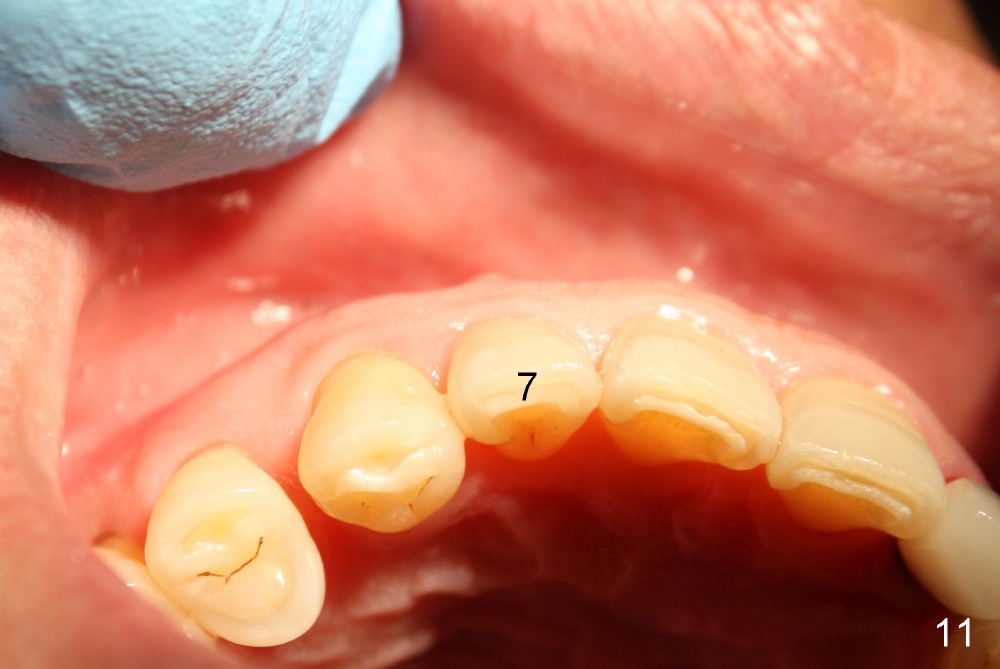

1. Place implant as lingual and apical as possible, cosmetic

5. Crown form for temporary, intentionally off occlusion

6. Provisional keeps papillae in place